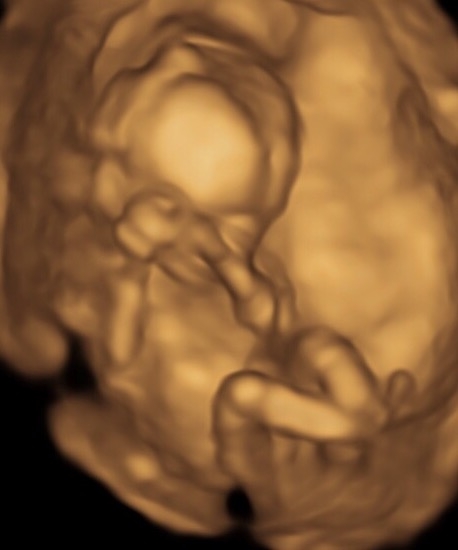

I am new here so bear with me lol. Has anybody got any knowledge on the nub/skull theory please. Can it really determine the gender. I'm due to find out Tuesday but just curious I suppose. This is my baby at 14 weeks 2 days. Any information or input would be greatly appreciated. Thanks.